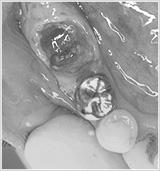

- 治療前の診断

痛みのあるブリッジ(銀歯)を外してみると、大きな奥歯が2つに割れていて、歯茎には膿が溜まっていました。自然と出血も続いています。

ここまでくると、残念ながら歯は抜かないといけません。 - インプラント治療